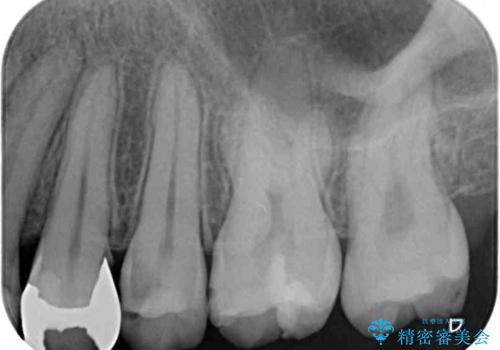

矯正治療後には、目立つ銀歯と隣接するむし歯をセラミックインレーにて修復治療することとしました。

左右ともに奥歯の咬み合わせには大きな問題がなく、窮屈な歯列を解決すれば歯列を整えることできたため、僅か1年で終えることができました。